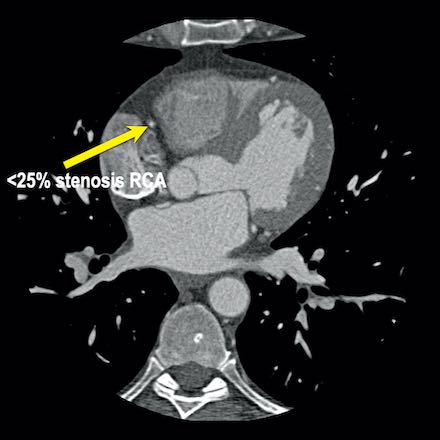

case 1 – CAD-RADS 2/P1

First, scroll through the scan.

Not all images are included. Some images without any abnormalities are skipped

from the series.

How would you describe the findings on the coronary CTA?

The findings are:

- Agatston score of

this patient was 14 (P1). Please, also note the calcification of the aortic valve. - Some partially

calcified and calcified plaques are present in the LAD with mild stenosis

(25-49%). - Calcified-plaque in

the LCX causing minimal stenosis (<25%). - Non-calcified

plaque in the distal RCA causing minimal stenosis (<25%). - This patient classifies

as CAD-RADS 2/P1, which means no further workup is needed.